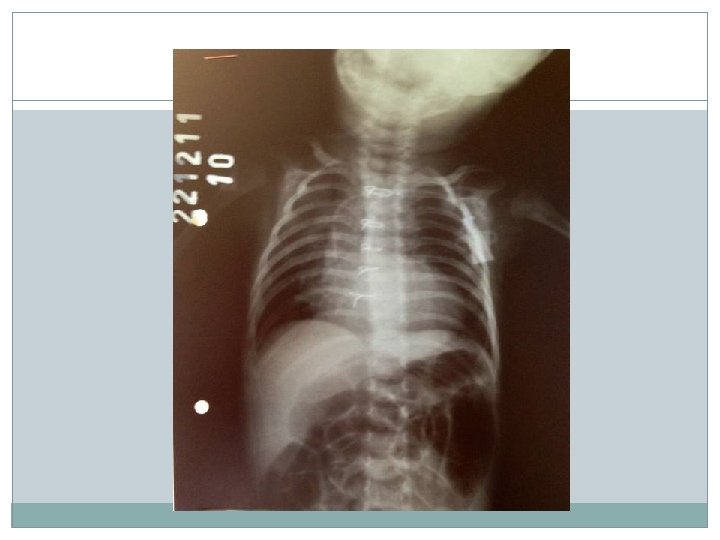

Diagnóstico RX de tórax: -Área cardíaca normal ou pouco aumentada; -Botão aórtico saliente; -Arco médio escavado (aspecto de “bota” ou “tamanco holandês”); -Ponta cardíaca acima do diafragma; -Vasos pulmonares pouco desenvolvidos, hilos pouco expressivos.